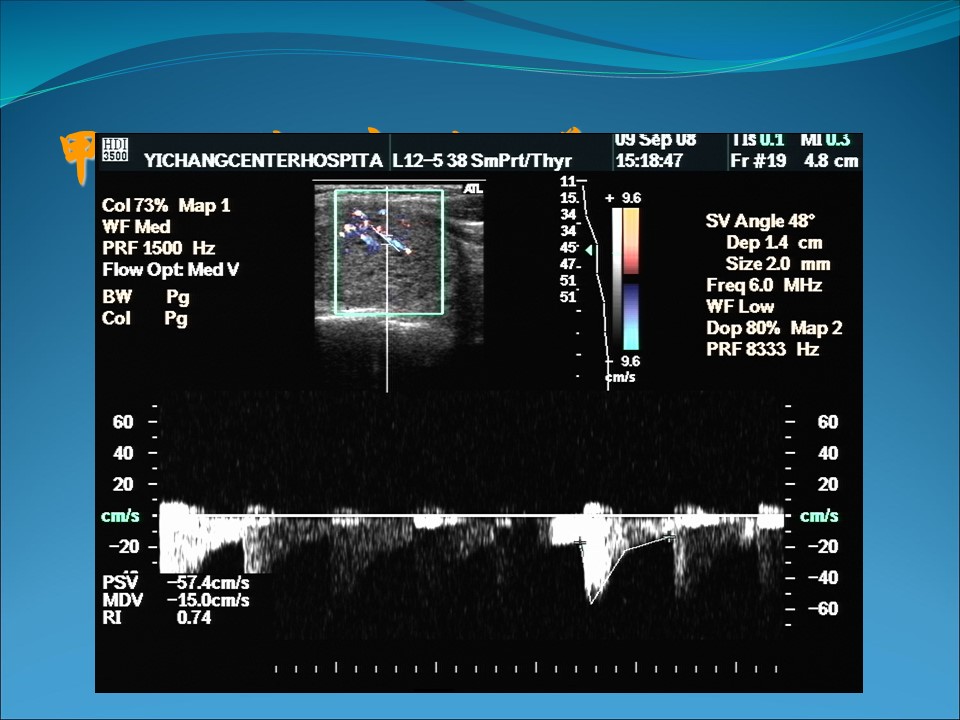

声像图特点:

4、CDFI:无特征性,偶可见血流信号增多、散在分布、无规律性。